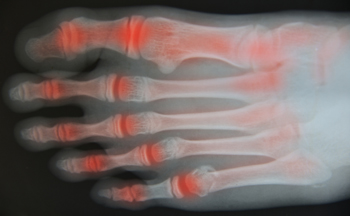

Rheumatoid arthritis and osteoarthritis are inflammatory joint-related conditions that can significantly affect mobility and daily comfort. Rheumatoid arthritis is an autoimmune disorder in which the immune system attacks joint tissues, leading to swelling, warmth, stiffness, and persistent fatigue. Osteoarthritis is a degenerative joint condition caused by gradual cartilage wear, often producing pain, stiffness, and reduced joint flexibility. Risk factors may include genetic predisposition, aging related changes, repetitive joint stress, previous injury, and inflammatory health conditions. Chiropractic adjustments may help lower inflammation by balancing the body's function through improved spinal and joint alignment, which supports nervous system communication and joint mobility. A chiropractor can also encourage better posture and movement patterns. If you have arthritis, and joint pain or stiffness affects your life, it is suggested that you consult a chiropractor for an evaluation and appropriate relief and management solutions.

Arthritis, a common condition affecting millions, causes inflammation, stiffness, and pain in the joints. It can make everyday activities challenging and significantly impact quality of life. While there is no cure for arthritis, chiropractic care offers a natural, non-invasive way to manage symptoms and improve joint function.

Chiropractors focus on enhancing joint mobility and reducing inflammation through gentle, targeted adjustments. By realigning the body and restoring proper movement, chiropractic care can help relieve the pressure on arthritic joints, alleviating pain and stiffness. Adjustments also support better circulation, which may help reduce inflammation around affected joints.

Chiropractic care can benefit both osteoarthritis and rheumatoid arthritis by focusing on reducing joint strain and promoting better movement.